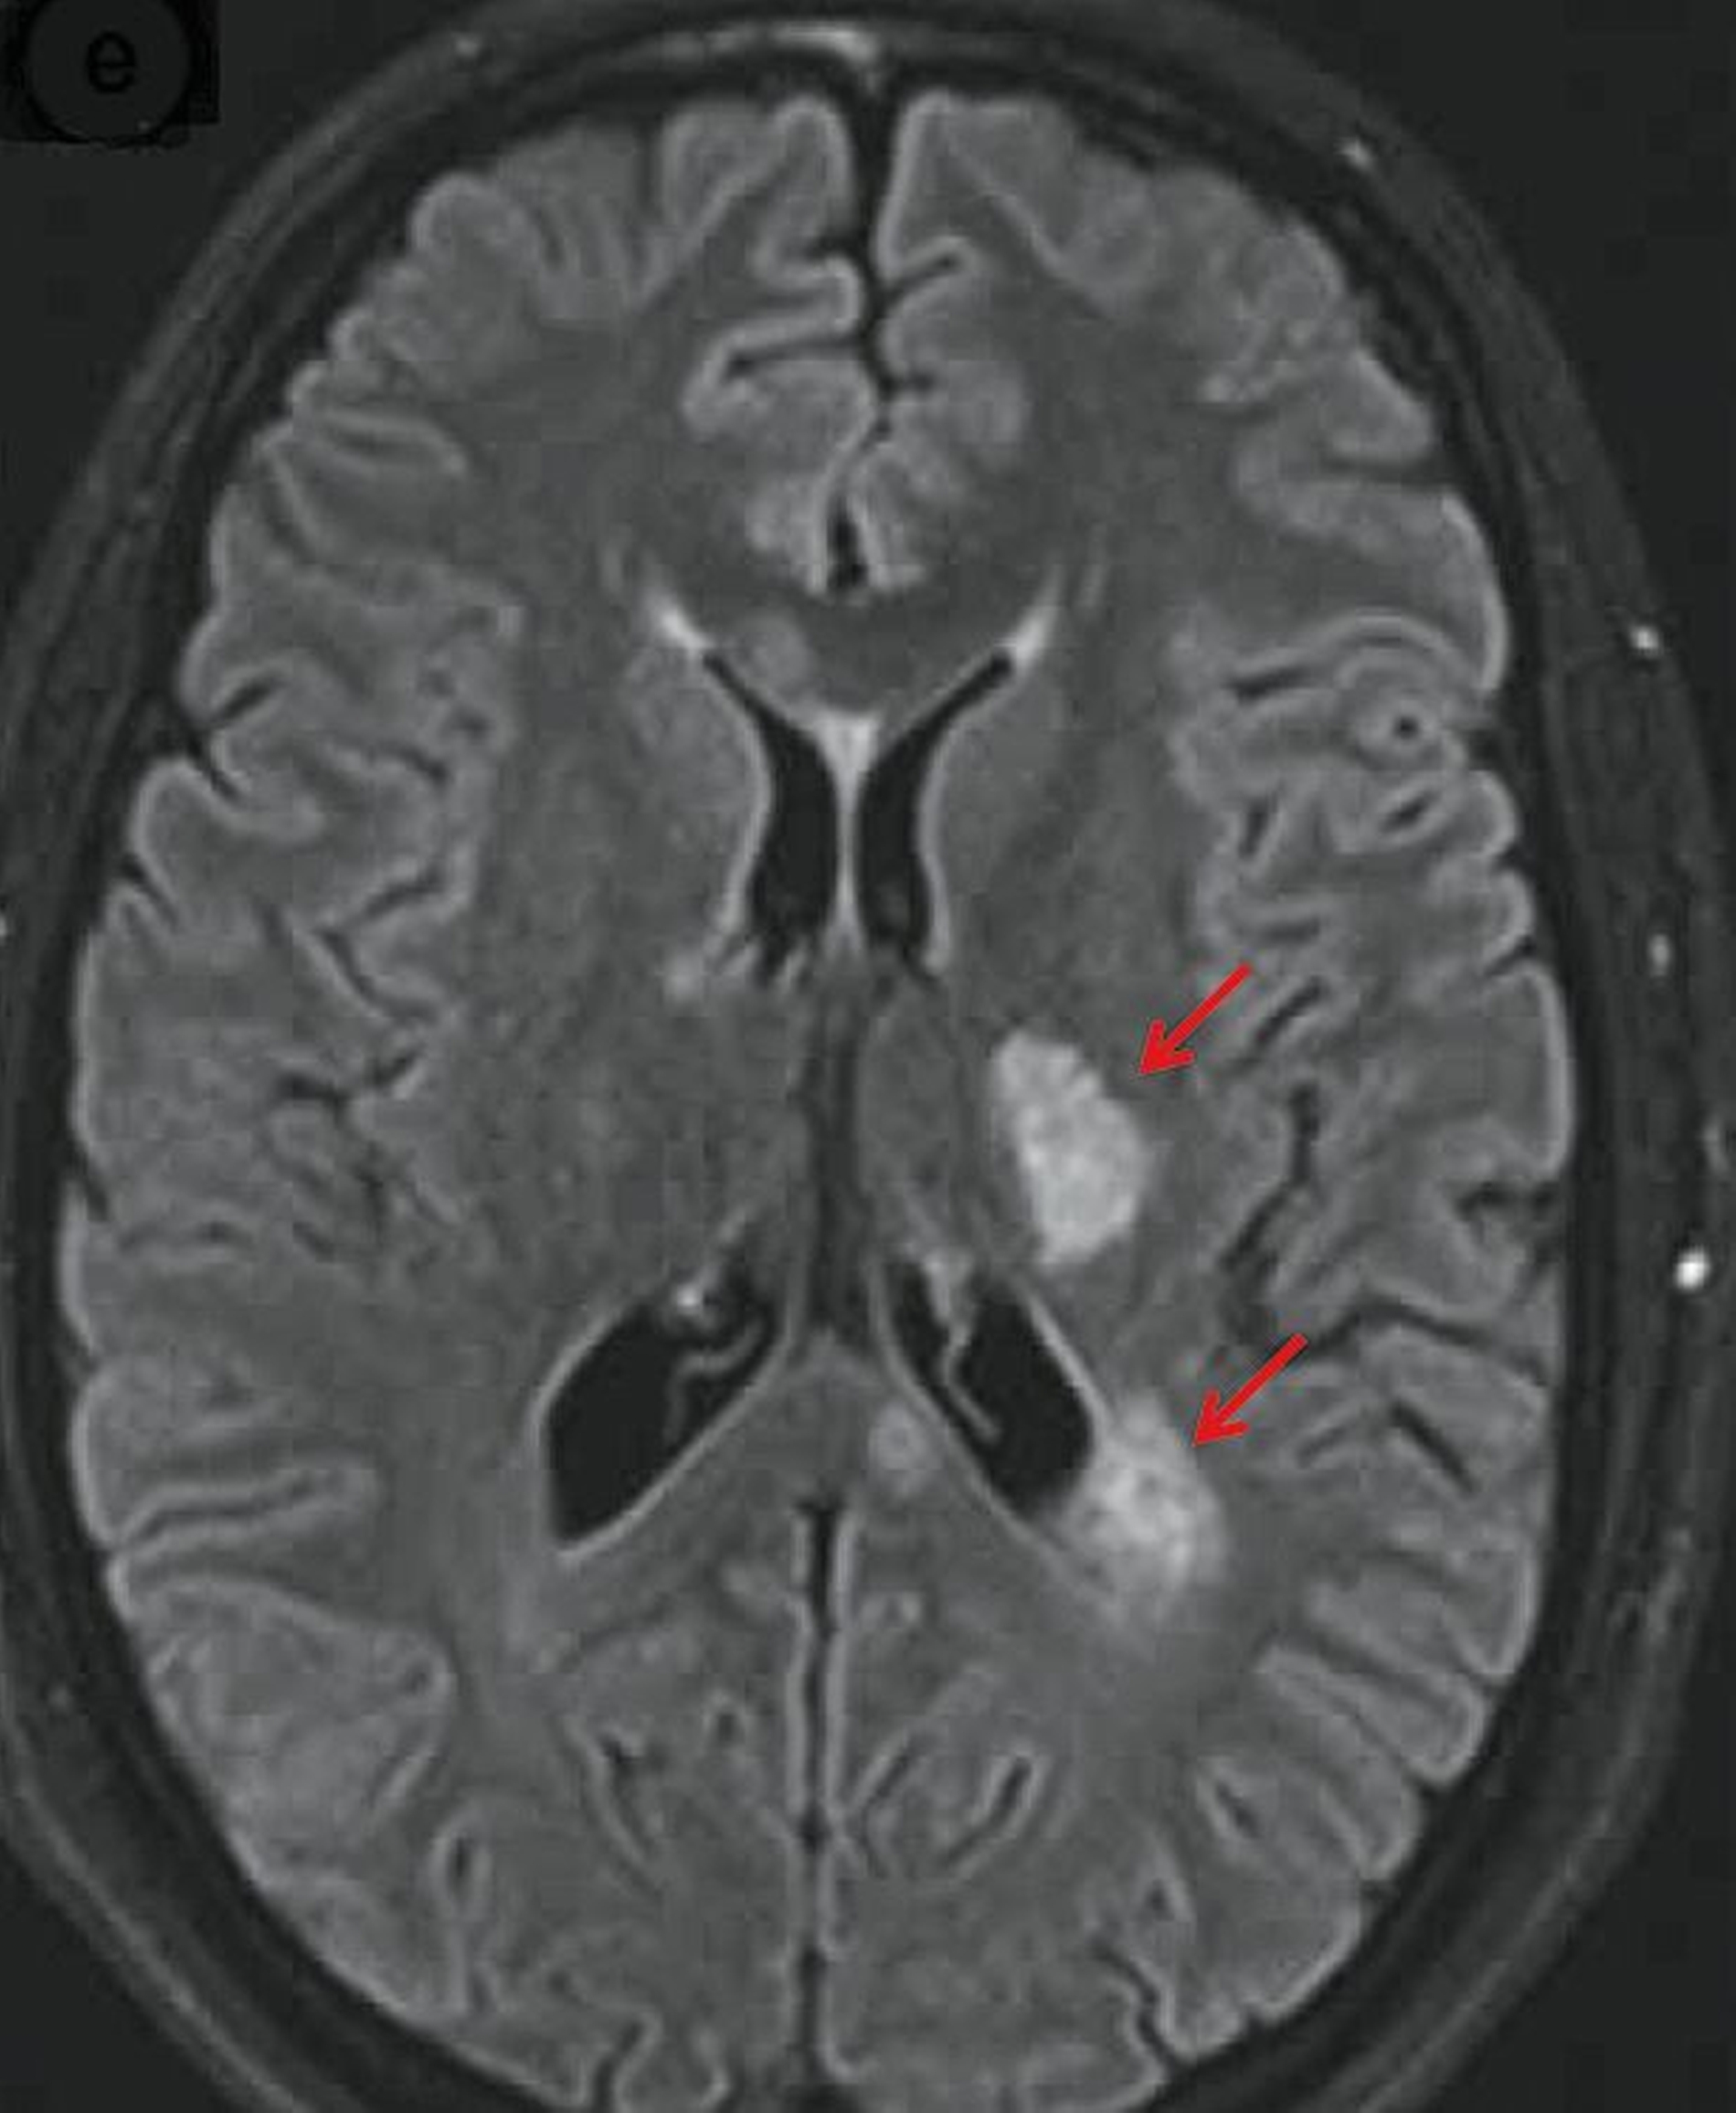

Zwei Tage später stellte sich die Patientin zur weitergehenden Diagnostik in der Abteilung für Neurologie vor. Inzwischen hatte sich das Taubheitsgefühl auf das Kinn und die Wange rechts ausgebreitet. Zusätzlich konnte in der klinischen Untersuchung eine Pallhypästhesie (herabgesetztes Vibrations-Empfinden) radial und malleolär rechts nachgewiesen werden. Laborchemisch ergab sich erneut kein wegweisender Befund. Es wurde eine kraniale Magnetresonanztomografie durchgeführt, die tatsächlich den Nachweis mehrerer T2-hyperintenser (FLAIR-Sequenz) Läsionen im intermediären Marklager beidseits frontal, periventrikulär links frontal, rechts paramedian pontin sowie am Übergang Medulla oblongata/spinalis erbringen konnte. In der Liquorpunktion ließen sich oligoklonale Banden (Typ 2) nachweisen. Die visuell evozierten Potenziale waren beidseits unauffällig. Die Tibialis sensibel evozierten Potenziale (SEP) und die Trigeminus SEP waren beidseits verzögert. In Zusammenschau aller Befunde ergab sich der dringende Verdacht auf eine entzündliche Erkrankung des zentralen Nervensystems, so dass eine intravenöse Therapie mit Methylprednisolon gestartet wurde. Im weiteren Verlauf bestätigte sich die Diagnose einer Multiplen Sklerose. Unter der weiteren Therapie zeigten sich die vormals beschriebenen Symptome vollständig rückläufig.

In Zusammenhang mit der Literaturrecherche zum hier vorgestellten Patientenfall ist ein Fallbericht zum sogenannten Numb Chin Syndrome von Interesse. Darin beschrieben die Autoren die Kasuistik einer 34-jährigen, sonst gesunden Patientin, die sich mit einem seit fünf Tagen bestehenden Taubheitsgefühl im Bereich des Kinns und der Unterlippe vorstellte. Nach Durchführung einer kranialen Magnetresonanztomografie zeigten sich Läsionen im Bereich der pontinen Fasern des Nervus trigeminus und multiple, periventrikulär gelegene, T2-hyperintense Läsionen. Eine Liquorpunktion ergab den Befund oligoklonaler IgG-Banden. Diese Befunde sprachen für eine demyelinisierende Erkrankung des zentralen Nervensystems, die sich im weiteren Verlauf als Multiple Sklerose mit isoliertem klinischem Befund herausstellte. Nach einer immunmodulierenden Therapie mit Beta-Interferon waren die Beschwerden rückläufig [Oestmann et al., 2008].